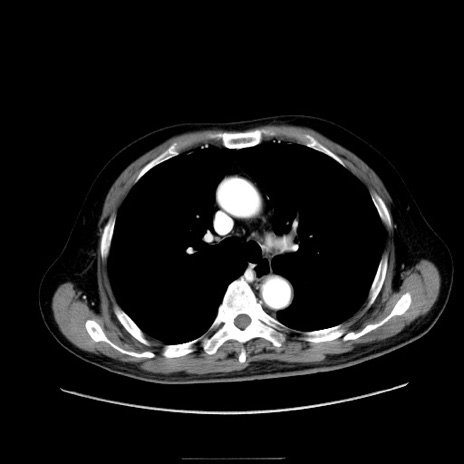

症例30(横断像)

【症例】80歳代男性

【主訴】臍周囲痛

【現病歴】約6時間前から臍下部痛が出現。次第に腹部膨隆・背部痛も生じてきたため来院。背部痛の場所は変化しない。

【既往歴】腎盂腎炎

【身体所見】意識清明、BT 36.3℃、BP  131/87mmHg、P 87bpm、SpO2 100%(RA)、臍周囲自発痛・圧痛あり、反跳痛なし、自発痛部位に一致して板状硬あり、腹部膨隆、腸雑音減弱、CVA tenderness両側陰性。

【データ】WBC 19600、CRP 0.33